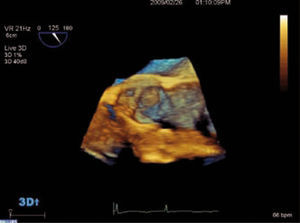

El ETE nos aporta información más detallada de la anatomía valvular y es necesario en casos en los que el ETT no sea diagnóstico. Con el ETE 3D podemos analizar la válvula y el chorro de IAo con mayor precisión (Figs. 11–14).